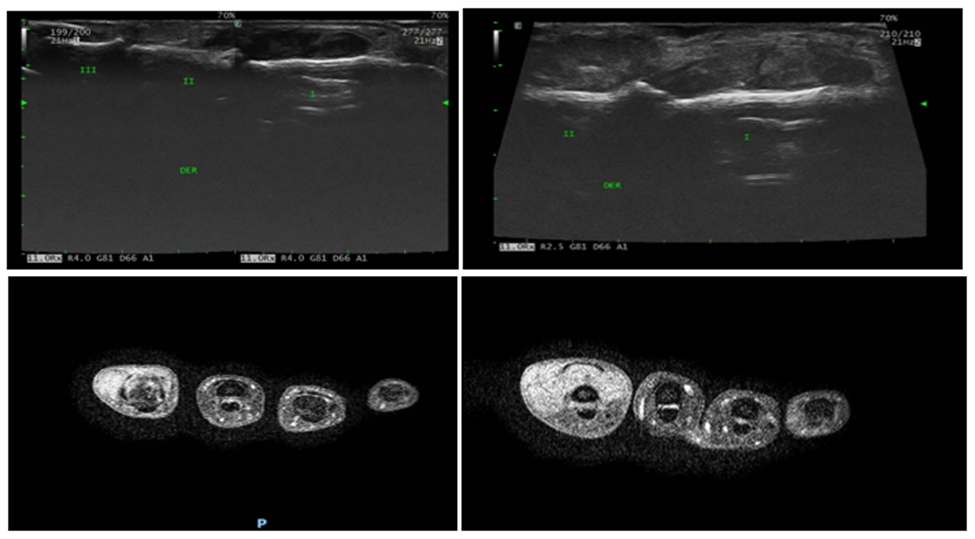

The clinical examination of the hand is the keystone of the diagnosis of GCTTS, however may be misdiagnosed or left without definitive diagnosis until intraoperative findings are available. There is no defined radiographic appearance. Ultrasonography shows a solid, homogeneous, hypoechoic tumor generally in relation to the flexor tendons of the fingers with increased vascularity on Doppler mode. Magnetic resonance imaging revels decreased signal intensity on T1- and T2 weighted images. Magnetic resonance imaging is the most definitive imaging study, however it is generally not obtained due to the ubiquity and cost-effectiveness of radiography and ultrasound (Figure 1). GCTTS differs from fibrolipoma of tendon sheath in the non-uniform signal, tumors with uniform signal are more likely to be GCTTS, secund fibrolipoma tumors are strip-like or irregular, while GCTTS are predominantly flaky/granular or separated (Figure 2) [9].

Figure 1: Ultrasound of giant cell tumor of the tendon sheath.

Figure 2: MRI of Affected Hand.